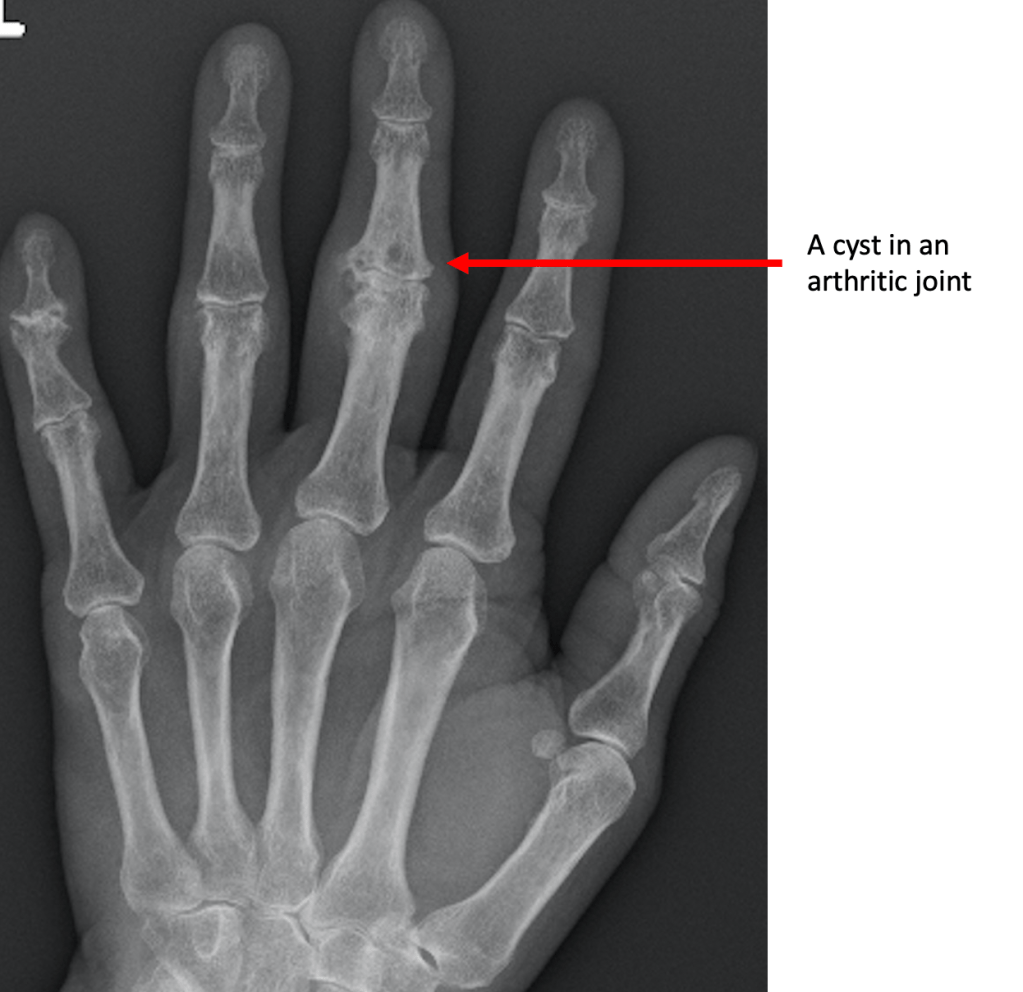

Cyst Formation

Cysts represent areas where the bone has been resorbed or dissolved away by the body. They occur around the arthritic joint, and are thought to occur in response to increased pressure around the arthritic joint. This, in turn, can interfere with the normal blood flow and facilitate cyst formation.